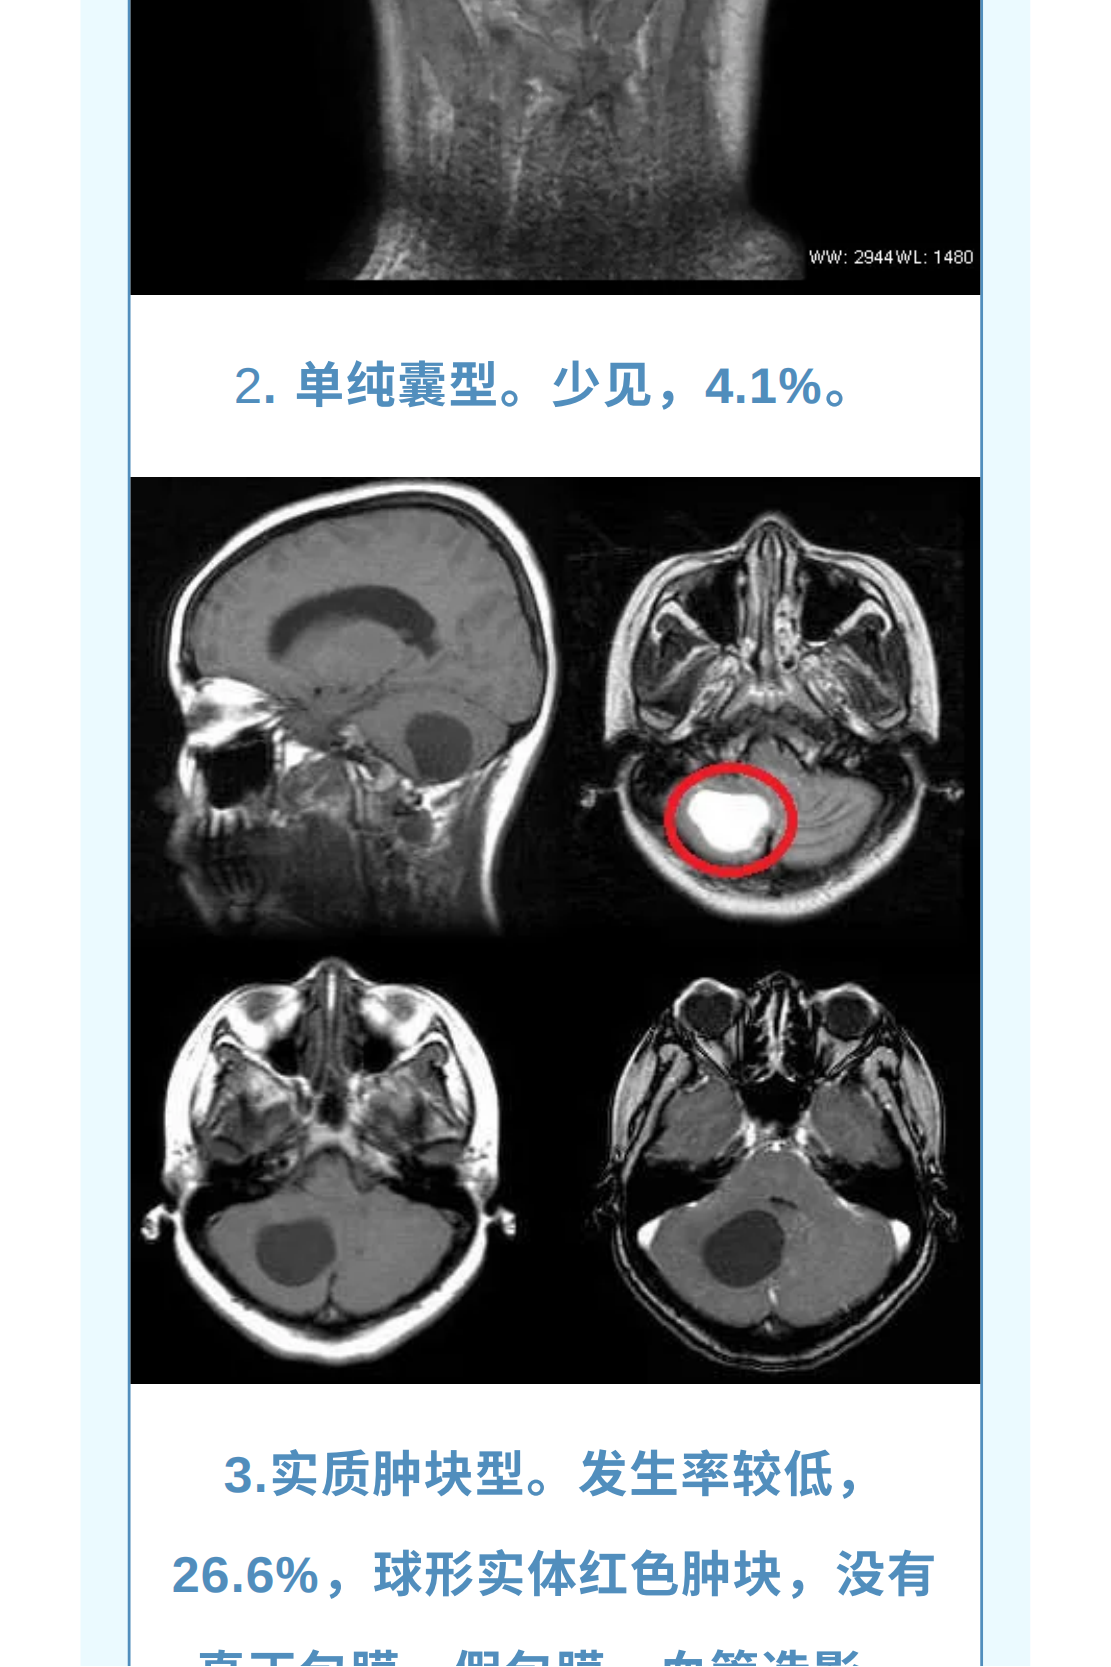

神经导航辅助下改良枕下天幕上入路治疗复杂小脑山坡实质性血管母细胞瘤

血管母细胞瘤( 血管网状细胞瘤、血管网织细胞瘤):为良性肿瘤, 有人认为其起源于血管周围的间叶细胞, 好发小脑中线旁,占颅内肿瘤的1%,后颅窝肿瘤的7%; 主要发生于成人(30~40岁多见);儿童期和老年人少见,男性较女性多见; 分为散发性和家族遗传性两种,后者表现为VHL病。多发者高度提示VHL病。